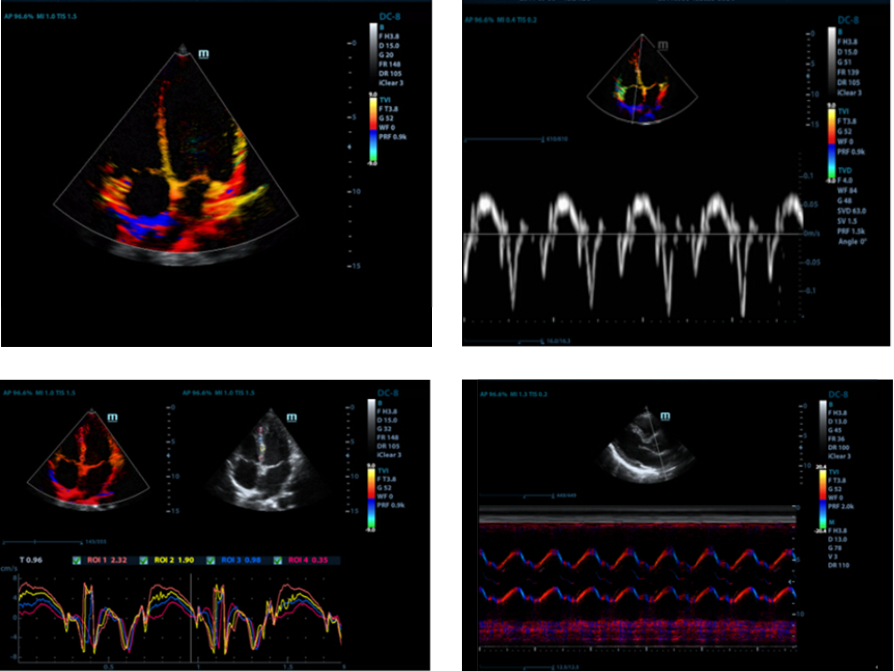

Free Xros CM?

Avalie com precis?o o movimento do mioc├Īrdio em diferentes fases e, simultaneamente, determine a sincroniza??o do mioc├Īrdio. A alta taxa de quadro proporciona resultados precisos:

TDI

O Tissue Doppler Imaging (Imagem doppler de tecidos) permite avaliar quantitativamente o movimento do mioc├Īrdio local e a fun??o, proporcionando modos TDI completos para diagn├│sticos mais r├Īpidos e diretos.